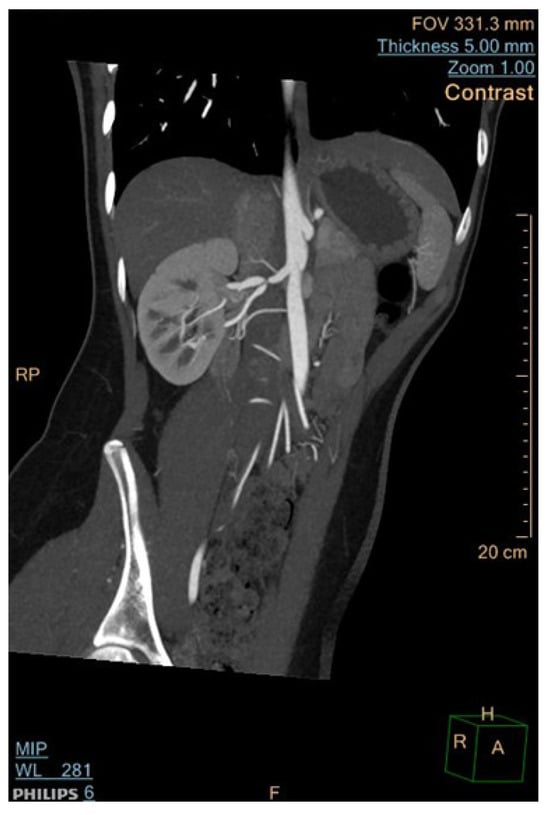

6.2. Computed Tomographic Angiography (CTA)

- Roebuck, D.J. Childhood hypertension: What does the radiologist contribute? Pediatr. Radiol. 2008, 38, 501–507. [Google Scholar] [CrossRef] [PubMed]